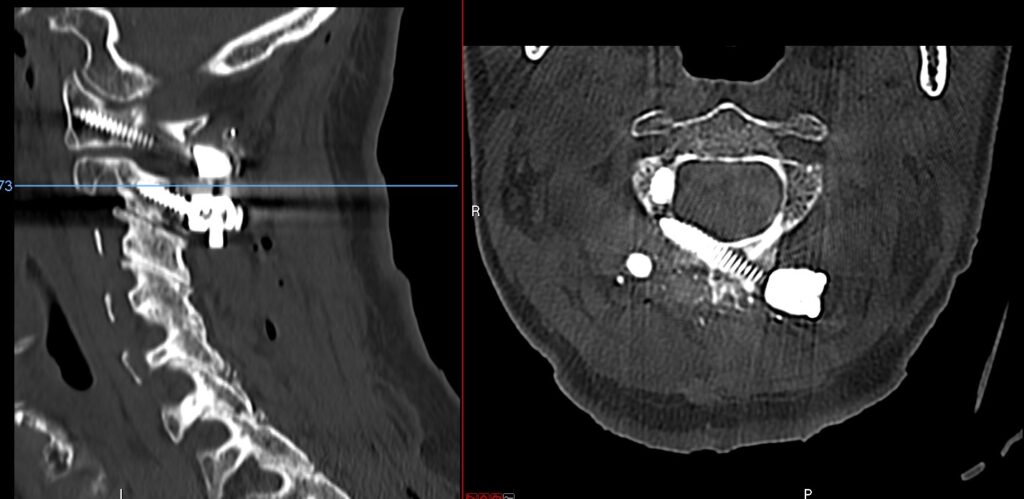

C1-2 fusion